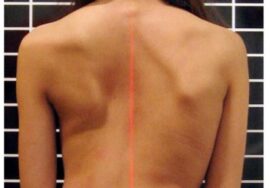

يُعد اعوجاج العمود الفقري مجهول السبب عند المراهقين (Adolescent Idiopathic Scoliosis – AIS) من أكثر اضطرابات العمود الفقري شيوعًا في مرحلة النمو، ويُعتبر العلاج بحزام اعوجاج العمود الفقري (Brace) الطريقة التحفظية الأكثر استخدامًا لتصحيح الانحناء ومنع تفاقمه.

إذا لاحظتِ علامات انحناء في ظهر طفلك، أو لاحظتِ عدم تماثل بين الجانبين، فلا تتردد الأن في استشارة مجانيه من طبيب متخصص.

إذا لاحظتِ علامات انحناء في ظهر طفلك، أو لاحظتِ عدم تماثل بين الجانبين، فلا تتردد الأن في استشارة مجانيه من طبيب متخصص.

إذا لاحظتِ علامات انحناء في ظهر طفلك، أو لاحظتِ عدم تماثل بين الجانبين، فلا تتردد الأن في استشارة مجانيه من طبيب متخصص.